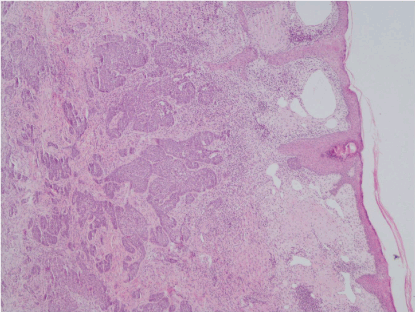

A punch biopsy was taken from the border of the mass and histopathological examination revealed a typical basal cell carcinoma with metatypic features (Figure 2) and the diagnosis of basosquamous BCC was established. The patient underwent a computed tomography of the head, where infiltration the bone, of the underlying tissues and of cervical or preauricular lymph nodes were excluded. The three smaller tumors on the patient’s face were diagnosed as BCCs based only on clinical features.

Figure 3. Histological picture of the tumor on the forehead showing nests of neoplastic cells in the mid and deep dermis with peripheral palisading without any considerable detachment of the dermis, compatible with metatypical bcc